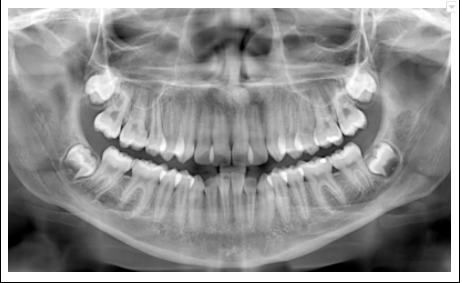

Por eso, necesitamos examinar y mirar toda la boca, incluyendo unas radiografías panorámicas (vea foto de radiografía panorámica) y no asistir sólo por dolor. Mire su boca desde un punto de vista de prevención, sin caries, sin tapaduras, sin ausencia de muelas, sin molestias musculares (bruxismo) de la boca, cuello o dolores de cabeza.